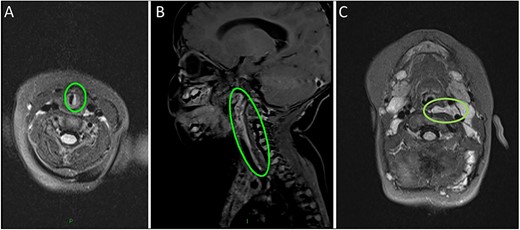

Surgery

On review of the imaging, the child underwent a biopsy of the lesion for a tissue diagnosis. Direct inspection revealed bulging of tissue from the left parapharyngeal space (Fig. 3). The mucosa was incised, constrictor muscles were divided and incisional biopsies were obtained. Histopathology samples showed lobules of haemangioma, strongly positive for GLUT-1 on immunohistochemistry confirming a carotid sheath infantile haemangioma. The patient continues to be followed up in the outpatient setting.

(A–C) Intra-operative endoscopic photographs highlighting the left sided asymmetric parapharyngeal fullness immediately inferior to the inferior pole of the left tonsil where the biopsy was undertaken and macroscopically abnormal tissue identified.